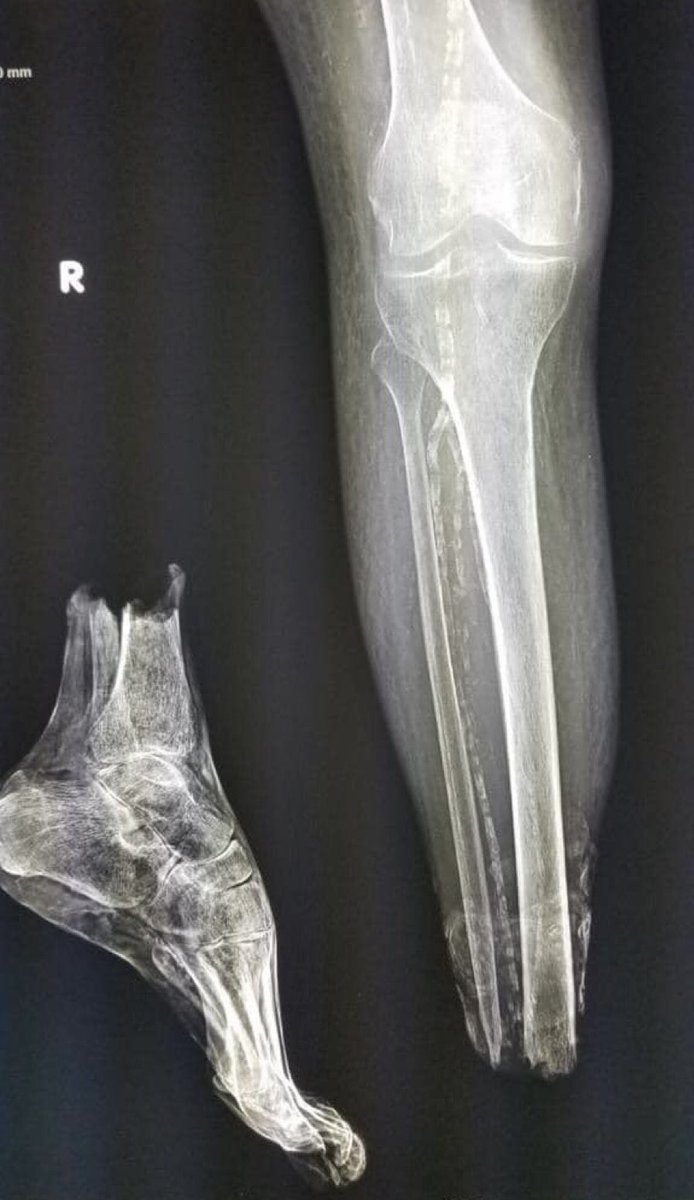

Sam Ghali, M.D.

Sam Ghali, M.D.@EM_RESUS·

Here’s a striking X-Ray that was sent to me with no clinical information What’s the diagnosis?

Sam Ghali, M.D. tweet media